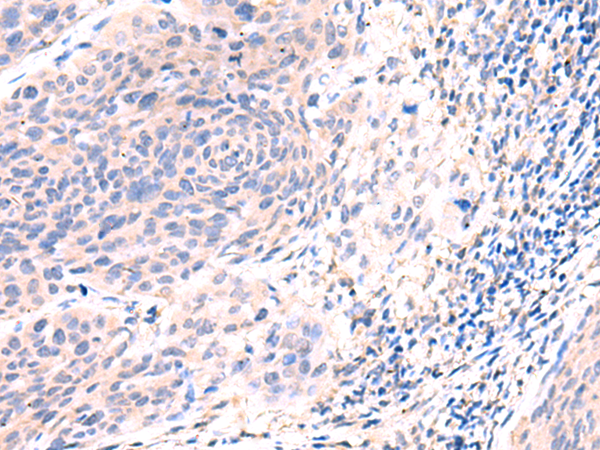

分类: 科研抗体货号: P08308别名: DRR1; TU3A应用: IHC反应种属: Human